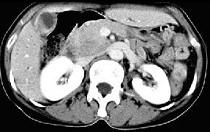

问题 患者,男,51岁,右上腹隐痛2月余,CT扫描如图,最可能的诊断是 ( )

选项 A.胆囊癌伴肝门胰头周围转移 B.胆囊息肉 C.胆囊黄色肉芽肿 D.慢性胰腺炎并胆囊息肉 E.胆囊腺瘤及慢性胰腺炎

答案 A